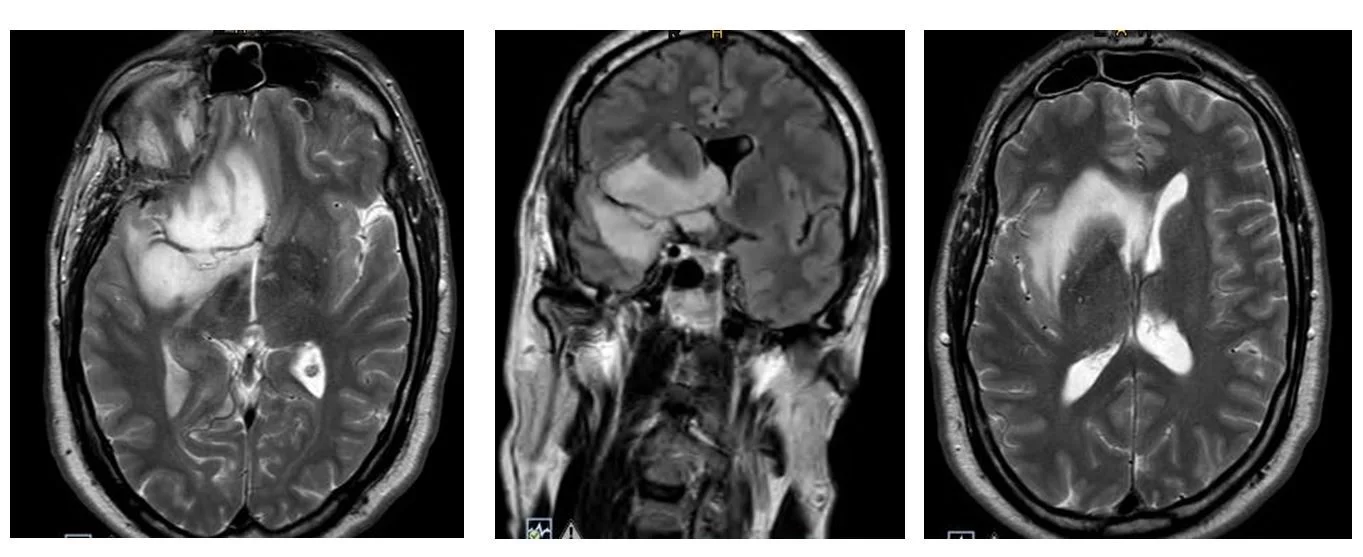

Ο γιατρός θα θελήσει να λάβει μια απεικόνιση του εγκεφάλου. Αυτό γίνεται είτε με μαγνητική τομογραφία είτε με αξονική τομογραφία. Μια σημαντική διαφορά μεταξύ μιας μαγνητικής και μιας αξονικής τομογραφίας είναι ότι η μαγνητική τομογραφία χρησιμοποιεί έναν μαγνήτη για να απεικονίσει τον εγκέφαλο, ενώ η αξονική χρησιμοποιεί ακτινογραφίες.Η μαγνητική τομογραφία συνήθως δίνει μια πιο λεπτομερή εικόνα του εγκεφάλου αλλά οι δύο εξετάσεις συνήθως είναι συμπληρωματικές.

Σε πολλές περιπτώσεις ίσως χρειαστεί να γίνει μετά την αρχική διάγνωση, και μια πιο εξειδικευμένη μαγνητική τομογραφία, με ειδικές ακολουθίες (δηλαδή με τη λήψη ειδικών εικόνων) προκειμένω να προσδιοριστεί με μεγαλύτερη ακρίβεια για τι όγκο ακριβώς πρόκειται καθώς επίσης και το αν ο όγκος βρίσκεται κοντά σε ευαίσθητες περιοχές του εγκεφάλου. Μερικές φορές τα ευρήματα στη μαγνητική τομογραφία είναι αρκετά σαφή και η διάγνωση χαμηλόβαθμου γλοιώματος είναι αρκετά πιθανή. Ωστόσο, σχεδόν πάντα συνιστάται βιοψία για τον καθορισμό του τύπου του όγκου που υπάρχει.